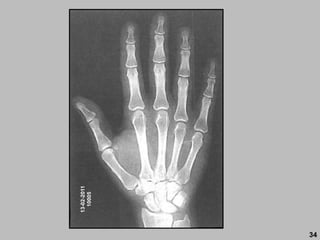

13-02-2011

10005

34